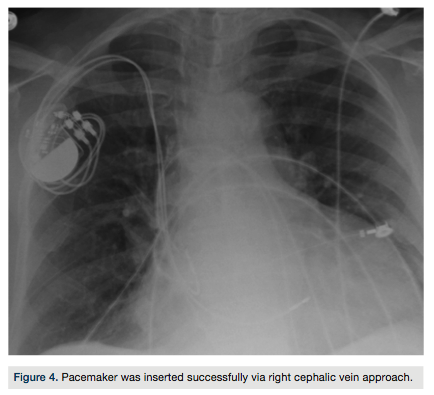

Under fluoroscopic guidance, a left cephalic vein approach was used to gain access to the transvenous route of the heart chambers. While inserting the guide wire, the left subclavian vein had an unusual course, and the guide wire crossed medially behind the heart, suggesting the presence of a persistent left superior vena cava, which was then confirmed by venography (Figure 3). Although a right ventricular pacing lead could still be

placed, an atrial lead could not be positioned superiorly in an optimal position via this approach. The left cephalic vein approach was abandoned and the pacemaker was successfully inserted via the right pectoral approach through the right cephalic vein (Figure 4).